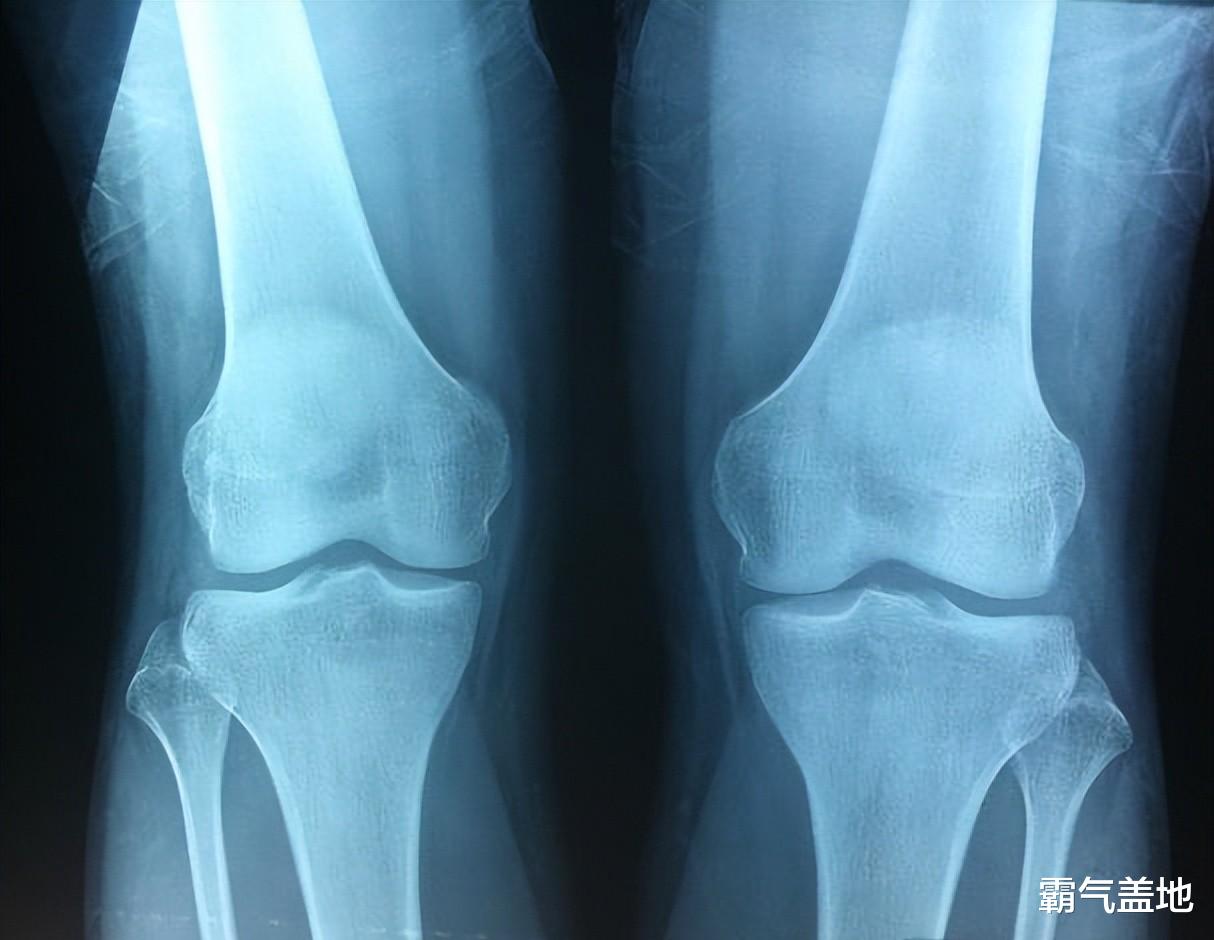

还有一些其他的“小前兆”也值得关注。 比如说,孩子的生长速度突然慢了下来,以前一年能长个5-10厘米,现在一年只能长个1-2厘米。 再比如,孩子的第二性征发育加速,女孩乳房开始发育,月经初潮;男孩喉结变大,声音开始低沉。 另外,孩子的脚丫子也可能不再“长大”,鞋码趋于稳定。 如果条件允许,可以带孩子去医院做个骨龄检测,看看骨龄是不是比实际年龄超前了。